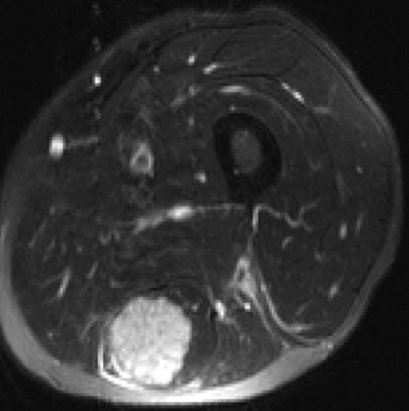

Figure 2 for case Adenocarcinoma lung metastasis

Figure 2